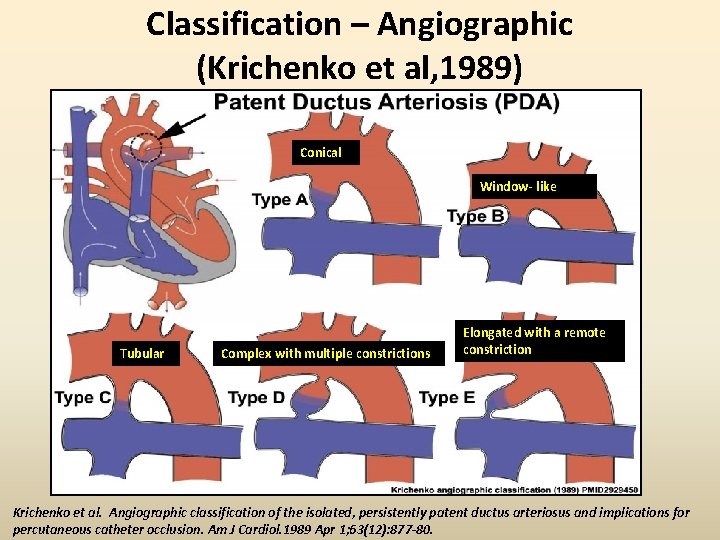

Classification – Angiographic (Krichenko et al, 1989) Conical Window- like Tubular Complex with multiple constrictions Elongated with a remote constriction Krichenko et al. Angiographic classification of the isolated, persistently patent ductus arteriosus and implications for percutaneous catheter occlusion. Am J Cardiol. 1989 Apr 1; 63(12): 877 -80.

Use of 2 D Echo in pre-interventional work up • Echo classification corresponding to Krichenko’s A- Conical with a narrow pulmonary end B- Short with narrow aortic end C- Tubular without constriction D- Multiple constrictions E- Long and tortuous requiring >1 echo plane for complete imaging Comprehensive Assessment of Patent Ductus Arteriosus by Echocardiography Before Transcatheter Closure. J Am Soc Echocardiogr 2002; 15: 1154 -9.

Echo classification • CONICAL DUCT ( common) • WINDOW DUCT • TUBULAR DUCT

Correlation of 2 D echo and Angio • Wong et al found poor correlation between colour Doppler and angiographic measurements 1 • 2 DE imaging overestimates the minimal diameter in comparison with angiography but in the majority difference was <1 mm 2 • In ~14% there is discrepancy in classification type 2 • Ampulla and length measurement were the most discordant 1. Wong et al. Validation of color Doppler measurements of minimum patent ductus arteriosus diameters: significance for coil embolization. Am Heart J 1998; 136: 714 -7. 2. Comprehensive Assessment of Patent Ductus Arteriosus by Echocardiography Before Transcatheter Closure. J Am Soc Echocardiogr 2002; 15: 1154 -9.